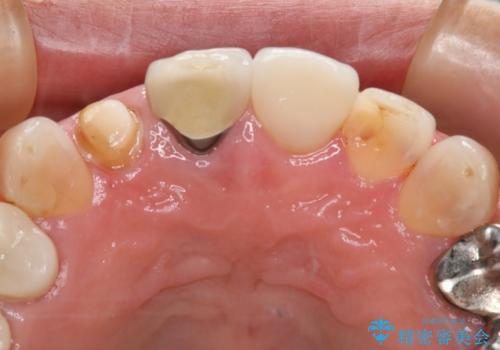

- 右上2番の審美性改善を主訴に来院された患者様です。

切削量と前歯ということからオールセラミッククラウンでの治療を選択しました。

前歯では審美性の高いオールセラミッククラウンでの治療を選択される患者様が多いです。